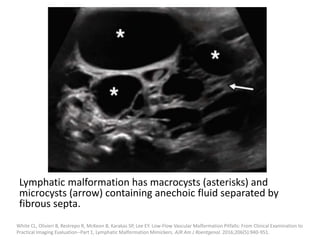

Imaging features

(a) Ultrasound:

Macrocystic LMs appear as thin-walled cystic

lesions with posterior acoustic enhancement

on US.

Thin septa are often present.

Characteristically, arterial or venous waveforms

are absent within the cysts on Doppler US, but

may be detected within the septa.

Behr GG, Johnson CM. Vascular anomalies: hemangiomas and beyond- part 2, slow-flow lesions. Am J Roentgenol. 2013;200:423-36.

Lymphatic malformation has macrocysts (asterisks) and

microcysts (arrow) containing anechoic fluid separated by

fibrous septa.

White CL, Olivieri B, Restrepo R, McKeon B, Karakas SP, Lee EY. Low-Flow Vascular Malformation Pitfalls: From Clinical Examination to

Practical Imaging Evaluation--Part 1, Lymphatic Malformation Mimickers. AJR Am J Roentgenol. 2016;206(5):940-951.